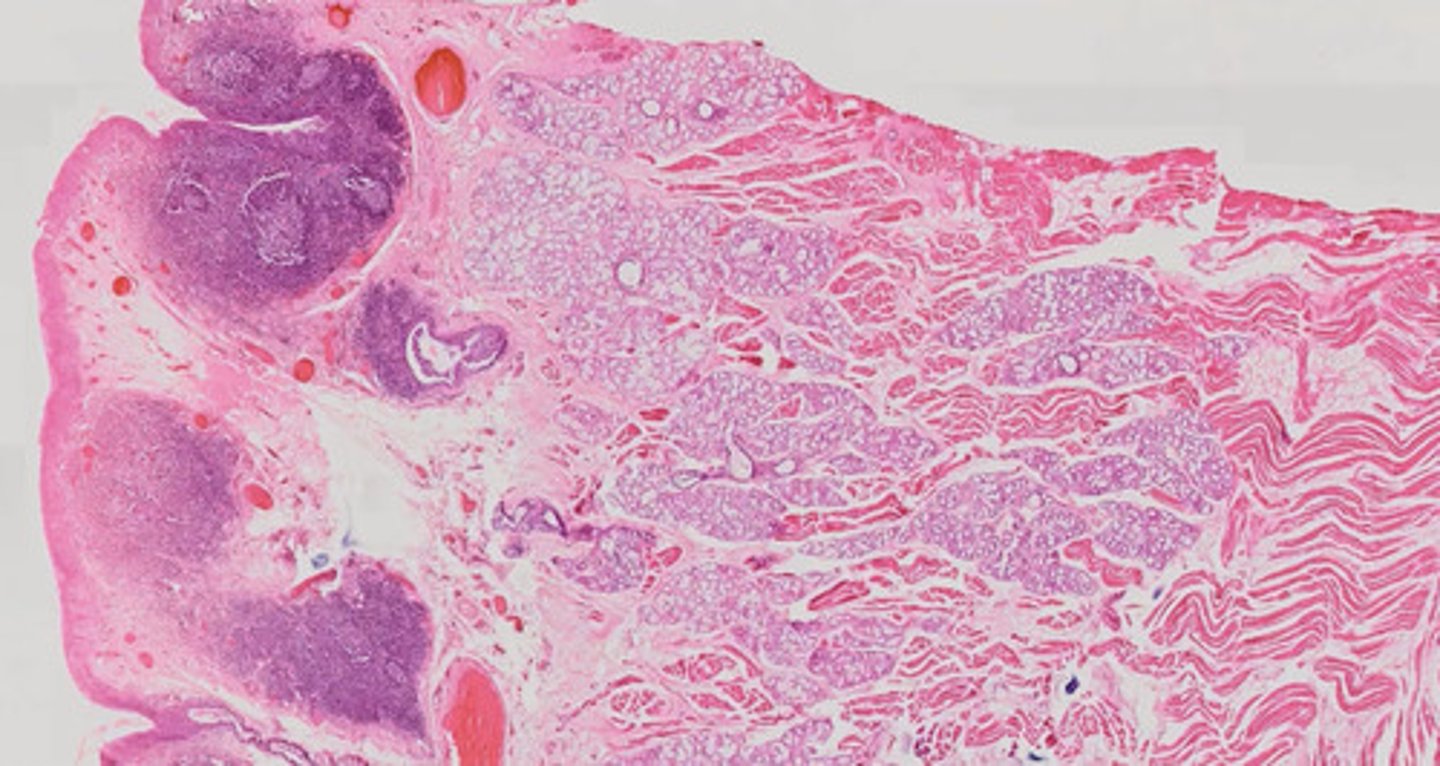

Węzeł chłonny (H+E)

Migdałek podniebienny (H+E)

Język - migdałek językowy (H+E)

Wyrostek robaczkowy (H+E)